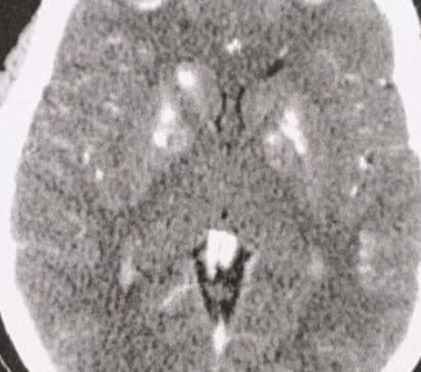

Acromegalia